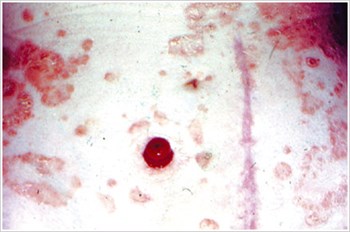

농피증 괴저(Pyoderma Gangrenosum)

설명/원인:

크론병이나 궤양성 대장염과 같은 염증성 장 질환(IBD) 환자에서 흔히 볼 수 있는 염증성 피부 질환.

조짐:

- 불규칙한 모양, 붉은색, 통증, 감염된 궤양, 빨간색에서 보라색으로 말린 가장자리; 다리, 엉덩이, 얼굴, 장루 주위 부위에 나타납니다.